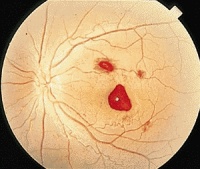

眼底出血

眼底出血不是一种独立的眼病,而是许多眼病和某些全身疾病所共有的特征。常见于高血压视

网膜病变、糖尿病及肾病引起的视网膜病变。视网膜静脉周围炎、视网膜静脉阻塞、视盘血管炎以及血液病引起视网膜病变,眼外伤性眼底出血。由于各种不同的病因导致相同的病理损害,如视网膜出血,渗出,微血管瘤、新生血管等。

(4)视网膜血管异常,各种不同的病因导致相同的病理损害,如视网膜出血、渗出、微血管瘤、新生血管等。

特点:出血开始或有反复出血倾向,发病时间多在15天内,视网膜上点片状出血或以视乳头为中心,放射状出血,颜色鲜红。